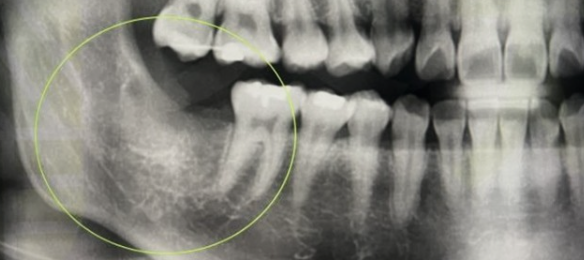

완전 매복 발치 : 36,600 ~ 37,900원 (2022년 일반 의원급 기준)

치아머리 부분이 치조골에 2/3 이상 매복된 상태로 치조골 삭제 및 치아 분할 술을 같이했을 경우입니다.

사랑니 발치 비용은 난이도에 따라 비용이 달라지며 매복이 심한 경우 발치가 불가능하기도 합니다. 난도가 높은 사랑니 발치 시 CT 장비를 갖춘 병원급 or 대학병원에서 발치하길 권장합니다. 사랑니 발치는 무조건 해야 하는 것은 아니며, 제대로 맹출 되었다면 제3대구치로 사용이 가능합니다.